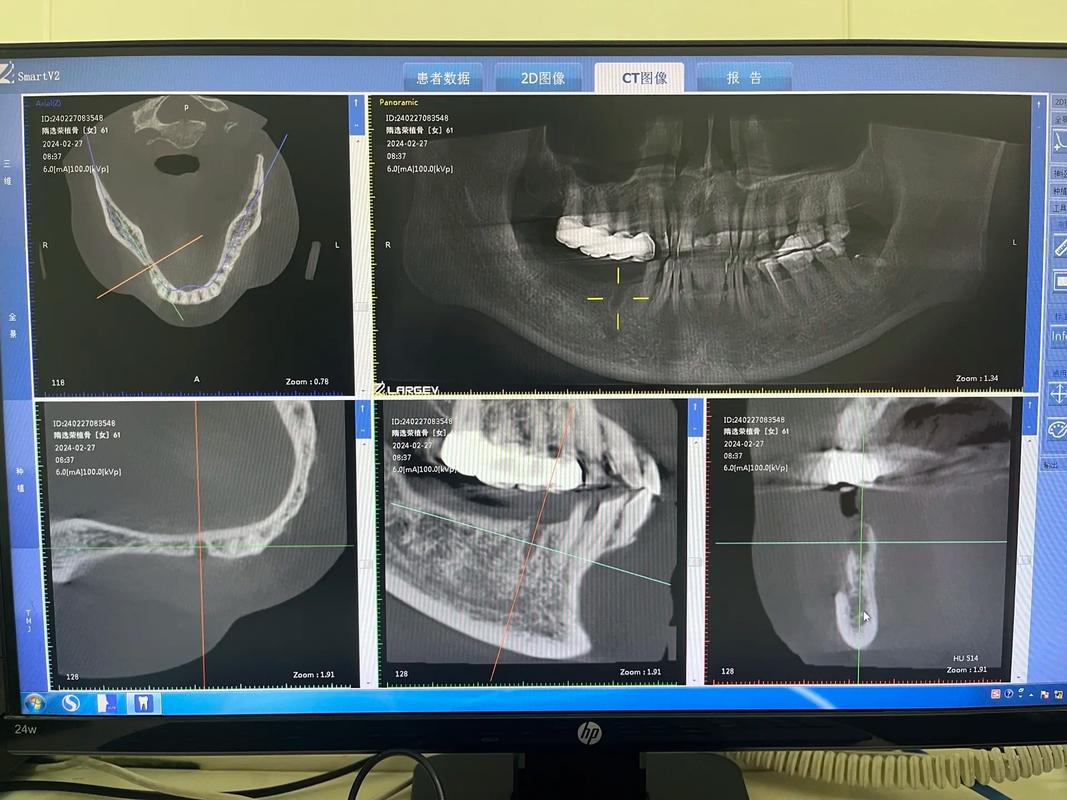

- 影像学检查:通过CBCT(锥形束CT)观察植骨区与自身骨的结合情况——理想状态下,移植骨与宿主骨之间无明显低密度影,骨小梁连续,密度接近自身骨,若骨结合不充分(如存在透射影),需继续等待。